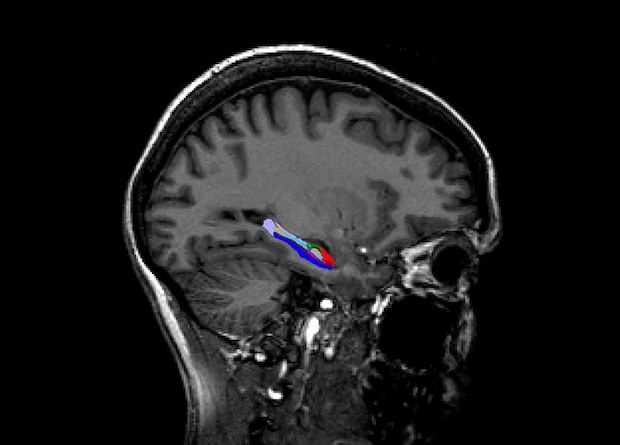

Мужской гиппокамп отличился от женского объемом отдельных структур

Австралийские ученые обнаружили зависимые от пола различия в объеме некоторых структур гиппокампа. Оказалось, что у мужчин, к примеру, больше парасубикулум, пресубикулум, фимбрия и гиппокампальная борозда, а вот у женщин чуть больше гиппокампальный хвостик. Различия наблюдались независимо от общего объема гиппокампа, что необходимо учитывать в будущих исследованиях анатомический структур, пишут ученые в журнале NeuroImage.

При этом не все исследования учитывают различия в общем объеме мозга и объеме отдельных больших структур в качестве побочной переменной, поэтому консенсуса по отсутствию или же наличию структурных различий некоторых участков в женском и мужском мозге чаще всего нет. Касается это, например, гиппокампа — участка головного мозга, который играет одну из важнейших ролей